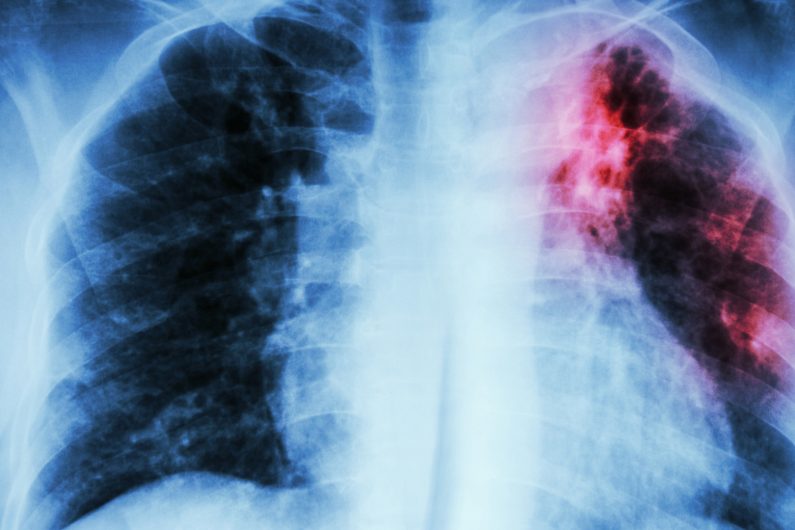

26 случая на туберкулоза в Пазарджишко

Общо 26 са регистрираните случаи на туберкулоза до края на ноември в Пазарджишка област, съобщиха от Регионалната здравна инспекция по повод кампанията за превенция на заболяването, която започва на 8 декември.